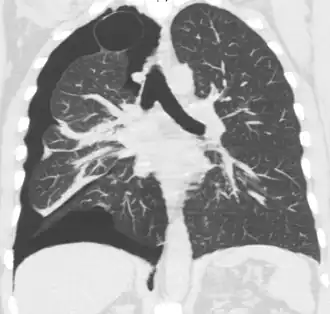

Chest X-ray

A plain chest radiograph, ideally with the X-ray beams being projected from the back (posteroanterior, or "PA"), and during maximal inspiration (holding one's breath), is the most appropriate first investigation.[35] It is not believed that routinely taking images during expiration would confer any benefit.[36] Still, they may be useful in the detection of a pneumothorax when clinical suspicion is high but yet an inspiratory radiograph appears normal.[37] Also, if the PA X-ray does not show a pneumothorax but there is a strong suspicion of one, lateral X-rays (with beams projecting from the side) may be performed, but this is not routine practice.[18][22]

It is not unusual for the mediastinum (the structure between the lungs that contains the heart, great blood vessels, and large airways) to be shifted away from the affected lung due to the pressure differences. This is not equivalent to a tension pneumothorax, which is determined mainly by the constellation of symptoms, hypoxia, and shock.[16]

The size of the pneumothorax (i.e. the volume of air in the pleural space) can be determined with a reasonable degree of accuracy by measuring the distance between the chest wall and the lung. This is relevant to treatment, as smaller pneumothoraces may be managed differently. An air rim of 2 cm means that the pneumothorax occupies about 50% of the hemithorax.[18] British professional guidelines have traditionally stated that the measurement should be performed at the level of the hilum (where blood vessels and airways enter the lung) with 2 cm as the cutoff,[18] while American guidelines state that the measurement should be done at the apex (top) of the lung with 3 cm differentiating between a "small" and a "large" pneumothorax.[38] The latter method may overestimate the size of a pneumothorax if it is located mainly at the apex, which is a common occurrence.[18] The various methods correlate poorly but are the best easily available ways of estimating pneumothorax size.[18][22] CT scanning (see below) can provide a more accurate determination of the size of the pneumothorax, but its routine use in this setting is not recommended.[38]

Not all pneumothoraces are uniform; some only form a pocket of air in a particular place in the chest.[18] Small amounts of fluid may be noted on the chest X-ray (hydropneumothorax); this may be blood (hemopneumothorax).[16] In some cases, the only significant abnormality may be the "deep sulcus sign", in which the normally small space between the chest wall and the diaphragm appears enlarged due to the abnormal presence of fluid.[19]